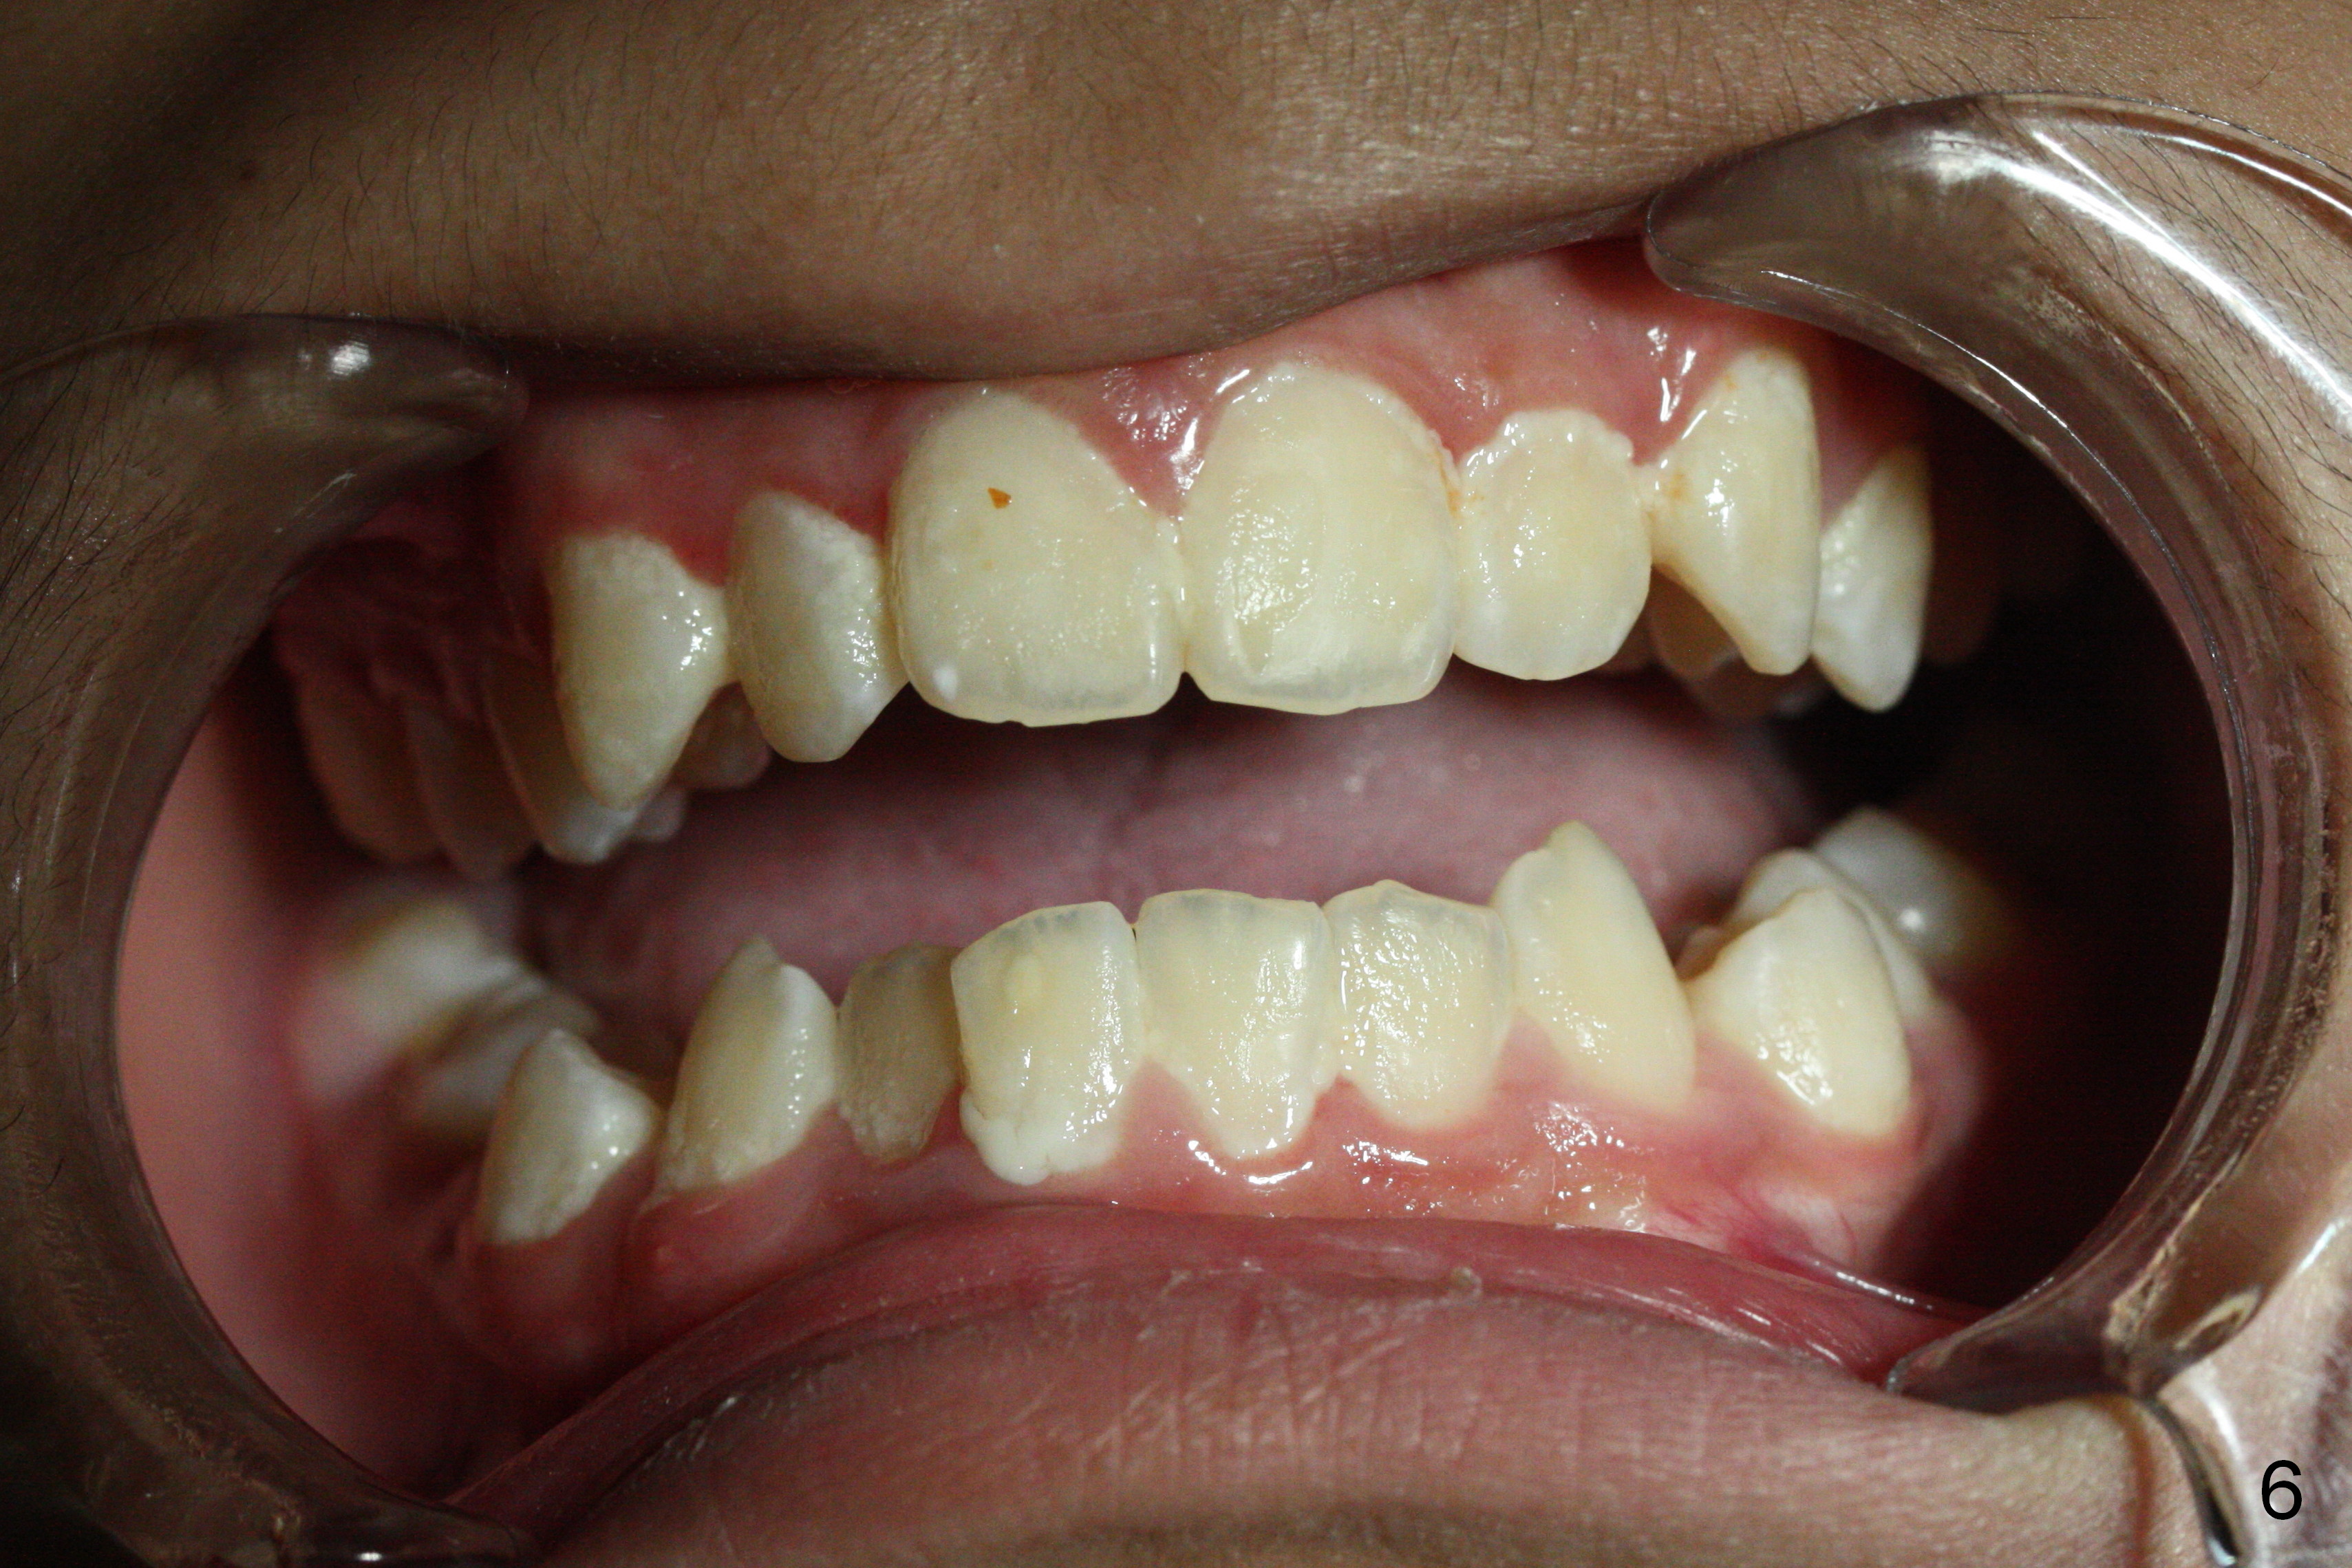

A 13-year-old man's malocclusion has two major components: upper midline deviation (Fig.2,5) and severe crowding (Fig.2,5-7).  His mother resists extraction, in spite of facial profile analysis (Fig.4,4').  A second obstacle to orthodontic treatment is his poor oral hygiene (Fig.5-7).  Before prophylaxis on Monday, can we decide together whether his oral hygiene has been improved drastically over the weekend?  If not, banding and bracketing will be canceled on Tuesday.